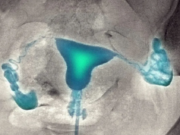

Когда нужно делать эхосальпингоскопию

Эхосальпингоскопия часто используется в диагностике бесплодия, помогает выявить спайки, гидросальпинкс и другие патологии, препятствующие зачатию. В отличие от рентгеновской гистеросальпингографии, ЭССГ менее болезненна, не...